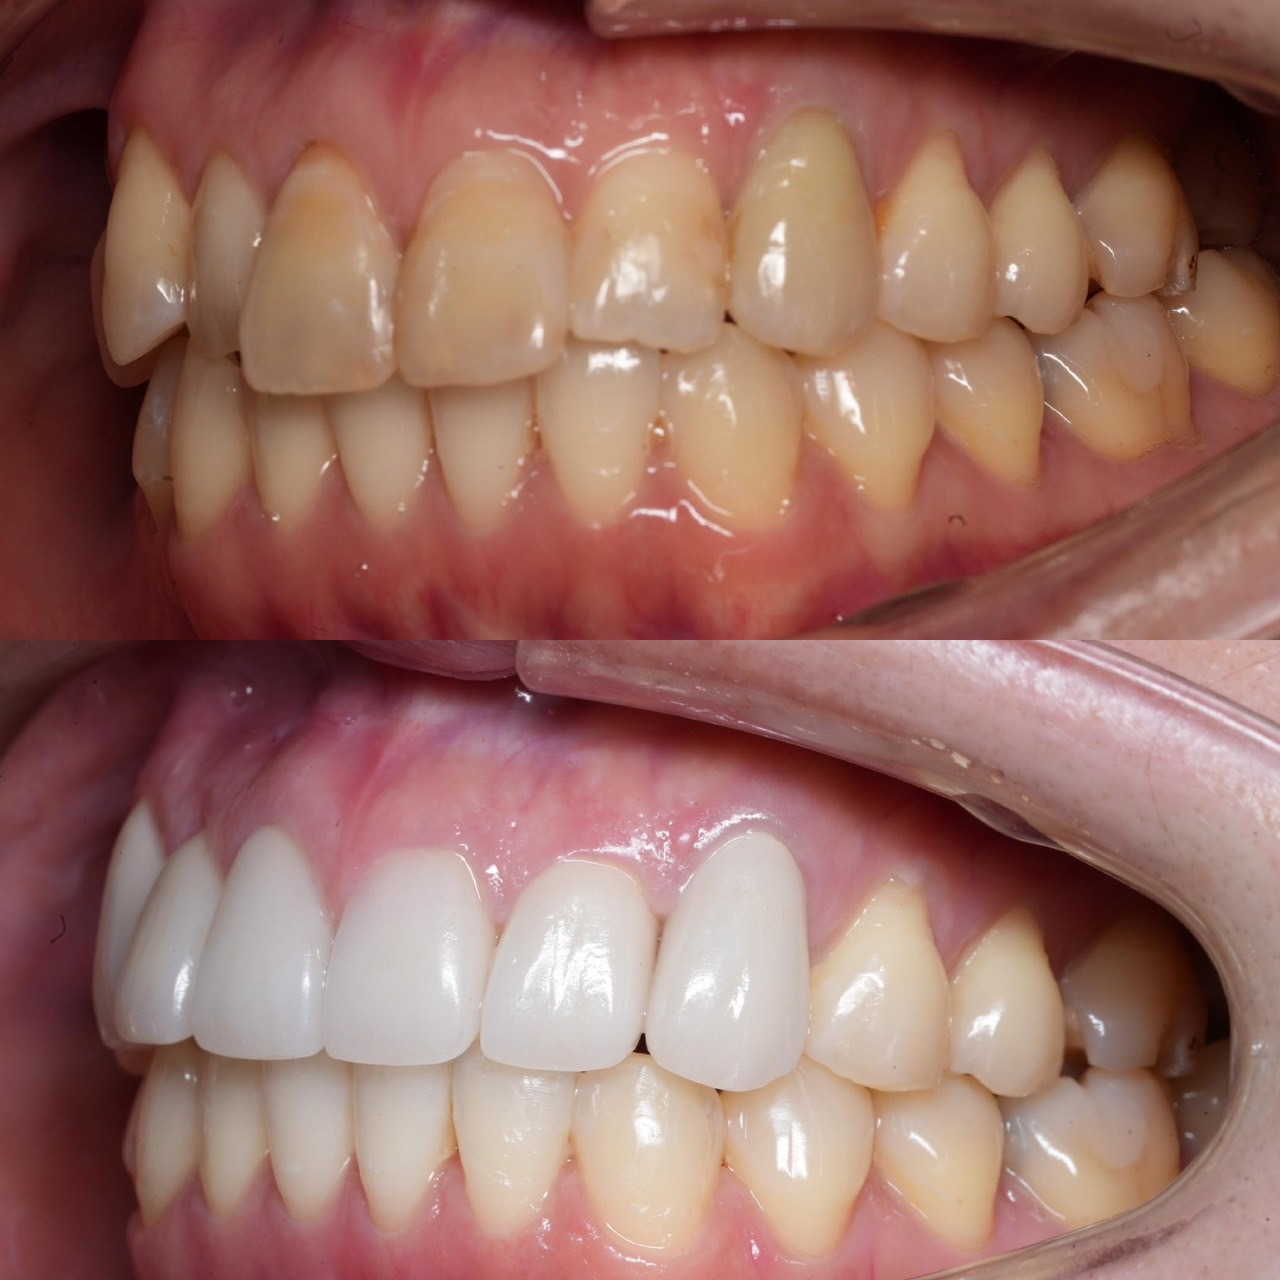

Case029

セラミック矯正の患者様です。

・上下の歯の入れ違い

・正中の歪みと隙間

を主訴にご来院くださいました。

この患者様は若年性歯周炎にかかってしまったため、一生懸命に歯を磨き、口の中は綺麗なのにも関わらず歯茎が下がってしまい、隙間が出来てしまっています。

これは矯正治療で歯の並び方を変えても絶対に無くなりません。

そのため、患者様の主訴を叶えるためにセラミック矯正で治療計画を練りました。

前のクリニックでは「上下一本ずつ抜糸してブリッジで矯正する」という計画だったようですが、

・患者様が非抜歯を希望されていること

・歯を抜かなくても綺麗に並べられそうだったこと

を理由に、当院では上は抜かずにセラミック。下は形態修正だけで対応しました。

この方針変更だけでもお値段も安く、また侵襲(ダメージ)を少なくすることができました。

治療の結果、最低限の侵襲で、見違えるほど綺麗な口元に治療することができ、患者様もとても喜んでくださいました。

【主訴】

・上下で入れ違っている前から2本目の歯のすれ違いを治したい。

・清潔感のある白さで明るい綺麗な口元にしたい

・歯の隙間を無くしたい

【ご要望、ご状況】

・歯を抜かずに治したい

・前医では上下1本ずつ抜歯をして、ブリッジで上3本、下3本の計6本を治すことを提案された。

【今回の治療法】

・右上の犬歯から左の前歯までの計4本をジルコニアセラミックで治療

・色は自分の歯よりやや白いくらいでホワイトニングをしてもしなくても大丈夫なくらいの白さ

・歯は抜かない

・右下の歯は形態修正だけで対応

・歯茎のラインを歯肉整形術で整える